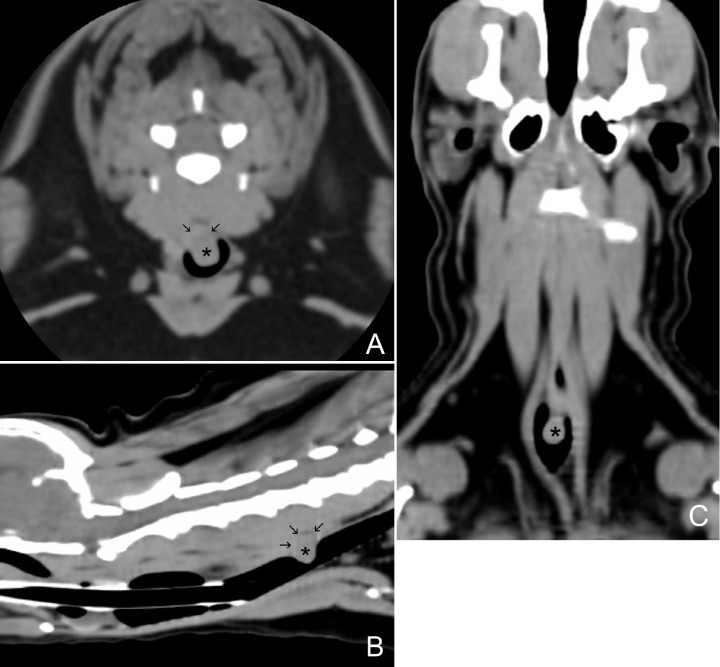

Posteriormente, se realizó una Tomografía Computarizada (TC) donde se evidenció que la masa visualizada previamente no solo protruía hacia el interior de la luz traqueal, ya que presentaba una pequeña extensión dorsalmente (Fig. 6). La masa era ligeramente hipoatenuada (50 UH) en relación con la musculatura paraespinal (62 UH) y sus dimensiones aproximadas eran de 0,9 cm (altura) x 0,75 cm (longitud) x 0,5 cm (anchura), no observándose evidencia de metástasis o invasión a estructuras adyacentes, y percibiendo los linfonodos y el parénquima pulmonar sin alteraciones evidentes.

Figura 6

Imágenes de tomografía computarizada (TC) en plano transversal (A) y reconstrucciones en planos sagital (B) y dorsal (C) en ventana de tejidos blandos del cuello del paciente, en las que se puede visualizar una estructura redondeada de atenuación tejido blando (50 UH), de base ancha (asterisco) que protruye hacia el exterior e interior de la luz de la tráquea desde la pared dorsal, a nivel del cuerpo vertebral de C5 (flechas).

Una masa traqueal puede ser visualizada y valorada mediante radiografía simple de tórax y fluoroscopia, debido a que la presencia de aire que la rodea permite delimitar sus márgenes. Sin embargo, la TC y la traqueoscopia son las herramientas que más información aportan sobre el tamaño y las características morfológicas de la masa, aunque el diagnóstico definitivo solamente es posible mediante el estudio histopatológico.3 La traqueoscopia ofrece la posibilidad de evaluar el grado de obstrucción de la luz traqueal y el aspecto de la masa, y permite la toma de una muestra para estudio citológico o histopatológico.8 En este caso, no se tomó muestra vía endoscópica de la masa por el riesgo de edema/sangrado y complicaciones subsiguientes. Por otro lado, la TC es de gran ayuda para planificar la cirugía al aportar información sobre el grado de infiltración, la extensión de la masa y la posible presencia de metástasis locales y distantes.8 En nuestro caso, las imágenes tomográficas evidenciaron un mayor volumen de la masa al poder observar un crecimiento de la misma extra e intraluminal, y constató la ausencia de metástasis tanto a nivel pulmonar como en estructuras adyacentes. Consideramos una limitación del estudio el no haber realizado un estudio postcontraste que hubiera mostrado el patrón de realce de la masa y quizás nos hubiera proporcionado un diagnóstico presuntivo más certero/aproximado, ya que una masa tipo pólipo presenta captación de contraste de manera periférica o “en anillo”, una neoplasia tipo carcinoma suele mostrar un realce heterogéneo y los linfomas, por lo general, tienen captación homogénea de contraste.9